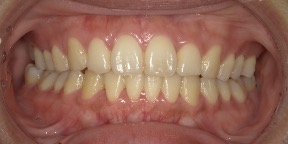

29歳女性のビフォーアフター

| 診断 | 叢生(デコボコがある状態)、過蓋咬合 |

| 治療方針 | インビザラインシステムにて主にIPR(歯と歯の間をわずかに削合してスペースを獲得する方法)を組み込んだ動的矯正治療を行い、叢生を改善後、保定を行う。臼歯部の咬合関係はプランの関係上維持して叢生と前歯部の咬合改善を目指した。 |

| 治療費 ※ | 60万4千円(診断、型取り、PMTC、保定装置を含む料金) |

| 治療期間 | 1年5か月 |

| リスク | 1日20時間以上マウスピースを使用できない場合、歯が動かない可能性がある。装着時や食事時に痛みを伴う。歯肉退縮や虫歯になるおそれがある。また、指導通りに装着できていない場合や適切なブラッシングが出来ていないとそのリスクが高くなる。歯根が短くなることがある。ごくまれに歯の神経が損傷してしまうことがある。過去にぶつけたり深い虫歯治療をしたことがあるとそのリスクはやや高くなる。矯正後には保定装置が必要。適切な使用ができない場合、後戻りの原因となる。将来的に歯並びが動いて再矯正が必要な場合がある。親知らずが正常に生えていない場合、その可能性がやや高くなる。 |